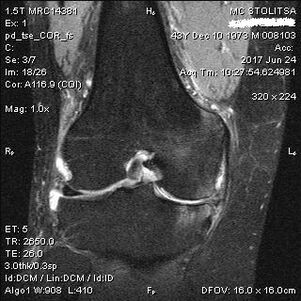

La diagnosi di artrosi dell'articolazione del ginocchio viene effettuata nello studio di un reumatologo o di un ortopedico. Il medico esamina l'articolazione interessata, la palpa, ascolta i reclami e pone ulteriori domande. Esegue diversi test, ad esempio chiedendo al paziente di piegare la gamba o di fare qualche passo. Se poi sarà necessario chiarire lo stadio della malattia o la natura delle alterazioni patologiche, vi indirizzerà ad ulteriori esami. Ad esempio per la tomografia computerizzata o la radiografia.